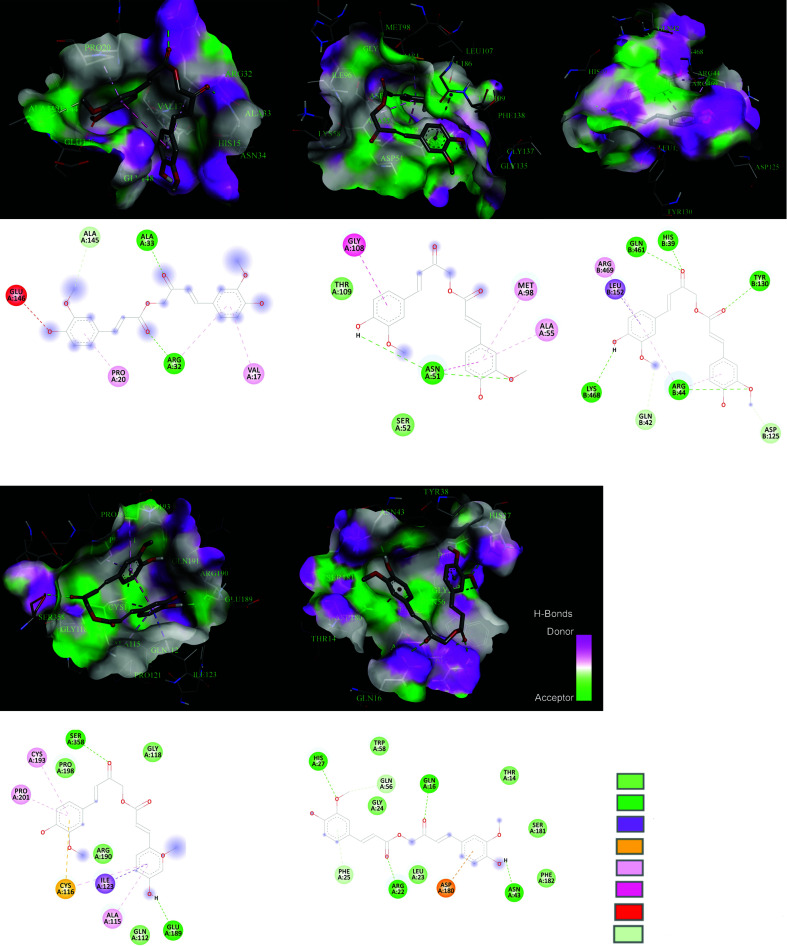

The 3D structure of Calebin-A (SDF format) obtained from PubChem (CID: 637429) is indicated in Fig. (7). The specification of the 3D structure of TP53, TNF, STAT3, HSP90AA1, and PTGS2 achieved from the PDB database is reported in Table 3.

Calebin-A binding site atoms interact with TNF, HSP90AA1, PTGS2, STAT3, and TP53.

The docking result of Calebin-A with TNF, STAT3, TP53, PTGS2, and HSP90AA1 was reported in Table 4, and their interactions were illustrated in Fig. (8). The results indicate that Calebin-A interacts with five essential hub proteins based on Binding Energy and H-bond observed. Calebin-A has a great binding with PTGS2 through five H-bonds and a binding affinity equal to -9.3 kcal/mol. It also indicated suitable interaction with STAT3 three H-bonds and -7.1 kcal/mol Binding Energy.

Calebin-A could potentially target TP53, TNF, STAT3, HSP90AA1, and PTGS2, which are implicated in NAFLD. In the gene expression (logFC: 0.91, P-Value: 9.04E-03) and PPI network (highest betweenness score: 0.23, Degree: 37, and Closeness score: 0.60) results, TNF was discovered as an essential hub gene involved in NAFLD that could be affected by Calebin-A. Docking analysis also indicated that Calebin-A could bind to the TNF-α (-6.5 kcal/mol) with two H-bonds, possibly suppressing TNF-α expression. TNF-α affects several processes connected to the pathogenic mechanisms of several human illnesses, including cellular activation and proliferation, inflammation, immune response, and cell death [63]. Calebin-A is crucial in controlling inflammatory responses and is connected to the pathogenesis of various inflammatory and autoimmune diseases [64]. Previous studies have shown that TNF-α is necessary for initiating NAFLD and its development into NASH by upregulating key molecules involved in inflammatory cytokines, lipid metabolism, and liver fibrosis [65]. Due to its role as the primary regulator of inflammatory cytokines, TNF-α has recently become recognized as a therapeutic target for several illnesses, including NAFLD. The development of NAFLD has been associated with activating pro-inflammatory cytokines, including TNF, in hepatocytes and adipose tissue [66]. Liver fat accumulation causes activation signals similar to the NF-kB via the upstream activation of IKK. TNF-α and other significant pro-inflammatory mediators are produced as a result of this activation, which induces the activation of Kupffer cells [67, 68]. TNF-α was highly up-regulated in the hepatocytes generated from mice fed with HFD. Earlier research also suggested that a high-carbohydrate diet (NAFLD-model) enhanced the amount of TNF-α in mouse liver [69, 70]. According to a randomized clinical trial, TNF-α was also considerably overexpressed in NAFLD patients [71]. Patients with steatohepatitis had greater blood TNF-α levels than healthy individuals with simple steatosis [72-74]. Moreover, the fibrotic stages were linked to the elevation of TNF and TNF-receptor-1 expression in the liver of patients with steatohepatitis [75]. In a preclinical study, Tomita et al. also confirmed that TNFR-deficient or TNF-deficient animal models of genetic or diet-induced NAFLD had better insulin sensitivity and less pronounced steatosis and fibrosis in the liver [76]. Calebin-A has been evaluated for its anti-inflammatory activity in several studies. Calebin-A could prevent IκBα degradation, nuclear translocation of p65-NF-κB, and NF-κB binding to DNA, thus preventing TNF-α induced canonical NF-κB activation [77, 78]. Other studies have reported that Calebin-A could block TNF-β like TNF-α [79-81].

In the pathogenesis of liver illnesses, the signal transducer and activator of transcription-3 (STAT3) plays a crucial role [4]. STAT3 belongs to the Janus kinase (JAK)/STAT pathway and is crucial in causing liver injury [82]. Deficiencies in STAT3 DNA-binding were reported to be mediated by increasing the expression of Pias3 in liver fibrosis [83]. STAT3 proteins were detected in high concentrations in the nucleus of proliferating biliary epithelial cells and hepatocytes from the liver of patients with cirrhosis [84]. STX-0119, a STAT3 dimerization inhibitor, was suggested to slow the progression of liver fibrosis by preventing the activation of hepatic stellate cells [85].

According to numerous investigations, STAT3 activity is also a survival signal that guards against lipotoxicity, whereas blocking hepatic STAT3 activation with other drugs reduces NAFLD-induced liver fibrosis [82]. In the NAFLD population, progressive fibrosis was linked to phosphorylation of STAT3, which is associated with an elevated risk for hepatocellular carcinoma (HCC) [86]. Recent research has shown that PNPLA3-mediated susceptibility to NAFLD was reduced by decreasing IL-6/STAT3 activity but increasing it in wild-type liver cells, promoting NAFLD onset. It was concluded that this function is due to bearing the rs738409 SNP that led to enhancing NF-κB activity, which is the cause of the heightened IL-6/STAT3 [87]. Calebin-A might regulate inflammatory pathways such as JAK/STAT3. The Janus kinases (JAKs), non-receptor cytoplasmic tyrosine kinases, are the primary promoters of STAT activation [17]. Several studies have suggested that curcumin may control the STAT3 signaling pathway. Most of these studies focus on STAT3's function in malignancies and the role of curcumin in suppressing them. Curcumin was shown to reduce STAT3 phosphorylation and block STAT3-mediated signaling [88]. In a previous study using an animal model of colitis, it was discovered that curcumin treatment drastically reduced STAT3 dimer DNA-binding activity and phospho-STAT3 activity [89]. A recent study found that STAT3 expression levels decreased in MDA-MB-231 cells following curcumin treatment [90]. By directly interfering with STAT3-mediated carcinogenesis, curcumin can abort atypical STAT3 activity [91]. However, no study has investigated the effect of Calebin-A on STAT3. In our PPI network analysis, we discovered STAT3 as a key protein interaction with a degree score of 31, a betweenness score of 0.58, and a closeness of 0.53, suggesting its importance in NAFLD. Calebin-A could modulate STAT3 through three H-bonds with a binding affinity energy of -7.1 kcal/mol.

TP53 is the genome's security factor, primarily as a tumor suppressor. It modulates a broad range of signaling pathways that inhibit oncogenic transformation [92]. p53 is thought to be a key player in the pathophysiology of NAFLD [93-98]. TP53 was discovered to be overexpressed in the livers of many NAFLD-plagued mouse models [98]. In normal sterol circumstances, TP53 directly and SREBP2 independently suppress the production of SQLE (squalene epoxidase), the first oxygenation enzyme and a rate-limiting step in cholesterol synthesis [99]. In mice given a HFD, TP53 activation was associated with hepatocyte apoptosis [96]. Moreover, in liver biopsy samples of human patients, there was a significant association between the degree of steatosis and p53 expression [97]. In a mouse model of NAFLD, the TP53 inhibitor pifithrin-p-nitro (PFT) caused attenuating steatosis, oxidative stress, and apoptosis [95]. According to these results, TP53 activation may be a widespread metabolic process that plays a significant role in the pathogenesis of fatty liver, regardless of the underlying cause, and that promotes apoptosis and oxidative stress and the development of harmful hepatic abnormalities like insulin resistance and steatosis. In one study, Calebin-A was shown to induce G2/M cycle arrest in human colon cancer cells by lowering the levels of the proteins cdc25A, cyclin A, cyclin B, and cdc2, and raising the levels of CDKIs like P21and TP53. Calebin-A also elevated levels of ROS, prompted a DNA damage response, and enhanced H2AX, chk2, and chk1 phosphorylation. Calebin-A administered intraperitoneally also dramatically reduced tumor diameter and volume [100]. Our obtained data displays that TP53 is one of the critical genes based on PPI network analysis (degree score: 40, betweenness score: 0.20, and closeness score: 0.63), which could be a possible target for NALFD. Calebin-A could strongly interact with TP53 by 6 H-bonds (-6.2 kcal/mol).

The HSP90AA1 is responsible for encoding heat shock protein 90α, which is triggered by stress and controls inflammation via several mechanisms. Previous research demonstrated that Hsp90α levels were higher in the serum of individuals with NAFLD, and there was a significant link between serum Hsp90 levels and steatohepatitis activity degree [101]. HSP90AA1 has been identified as one of the hub proteins in a PPI network analysis of GSE109836 [102]. In another in silico investigation of two datasets (GSE74656 and GSE62232), it was indicated that HSP90AA1 is a new pathogenic gene in the progression of NAFLD to HCC. The expression of HSP90AA1 was reported to be considerably decreased [103] in the liver of patients with alcoholic fatty liver disease (87). The level of HSP90AA1 could be repressed by curcumin administration [104]. However, there are no reports on the effect of Calebin-A on HSP90AA1. We observed HSP90AA1 as an effective hub gene in the PPI network, and the interaction with Calebin-A was through one H-bond (-6.9 kcal/mol).

The PTGS2 gene encodes an enzyme commonly known as cyclooxygenase two (COX-2) in the human body. The activation of PTSG2 has been linked to the etiology of several liver disorders, such as NAFLD, by enhancing hepatocyte lipid accumulation. Activation of PTSG2 after the establishment of type 2 diabetes and metabolic syndrome might have aggravating effects on the advancement of NASH [105]. PTGS2 is primarily associated with the role of gut flora in the onset and progression of NAFLD [106]. Calebin-A has been detected as a direct and non-selective inhibitor of PTSG1 and PTSG2 in several independent studies [10, 107]. As PTSG2 is one of the several NF-κB-dependent gene final products that play a significant role in many inflammatory processes, it is a main target for many traditional anti-inflammatory medicines [108]. PTGS2, discovered as an essential hub gene in DEGs and PPI network analyses, showed a strong interaction with Calebin-A (three H-bonds and a high affinity of -9.3 kcal/mol).